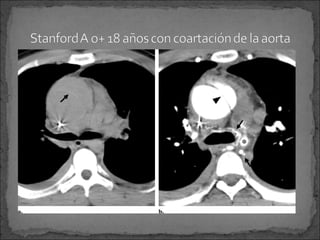

Stanford tipo A:

 75 por ciento

 Reparación inmediata para evitar complicaciones fatales

Extensión hacia el pericardio, espacio pleural, arterias

coronarias o al anillo aórtico valvular.

Stanford tipo B:

 Es tratada medicamente para HTA a menos que ocurra

alguna complicación -isquemia orgánica abdominal o

dolor persistente Cirugía

Coartación de la aorta

Stanford tipo A: 75 por ciento  Reparación inmediata para evitar complicaciones fatales Extensión hacia el pericardio, espacio pleural, arterias coronarias o al anillo aórtico valvular. Stanford tipo B:  Es tratada medicamente para HTA a menos que ocurra alguna complicación -isquemia orgánica abdominal o dolor persistente Cirugía